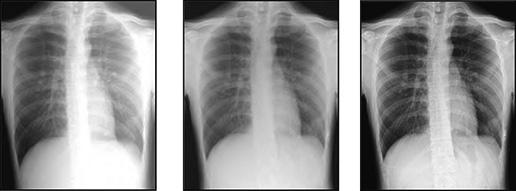

W artykule przedstawiono nową metodę przetwarzania zdjęć rentgenowskich – technologię Wirtualnej kratki, dzięki której słaba jakość zdjęcia wynikająca z rozproszonego promieniowania w przypadku wykonania zdjęcia bez kratki fizycznej ulega znacznej poprawie. Technologia ta poprawia jakość zdjęć rentgenowskich wykonywanych bez użycia kratki przeciwrozproszeniowej, zwykle przy zdjęciach przyłóżkowych oraz na SOR-ach. Kratki fizyczne są często używane w celu zminimalizowania wpływu…